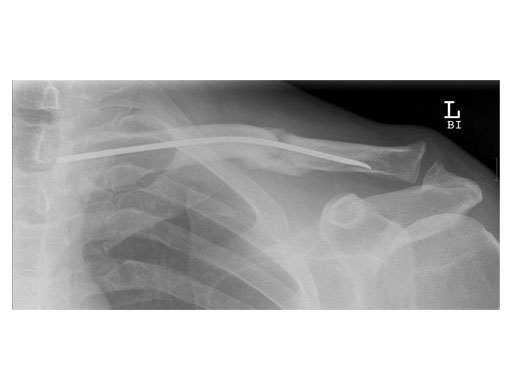

Case 2: 51 years, male, hit by tree

The operative technique as described by Rehm starts with a skin incision just above the sternal end of the clavicle. Approximately one cm lateral to the sternoclavicular joint, a hole is drilled into the anterior cortex. A titanium nail varying in diameter between 2.5 to 3.5 mm is mounted on a universal chuck with T-handle. With oscillating movements the TEN is advanced until it reaches the fracture site. If closed reduction manoeuvres are unsuccessful, an additional skin incision has to be made at the level of the fracture site enabling direct manipulation of the fragments.